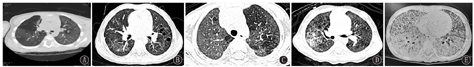

高分辨率CT(high-resolution computed tomography,HRCT)对发现肺间质性病变的敏感性高,GDSD的胸部HRCT常见表现为肺实质弥漫性磨玻璃影以及小叶内间质和小叶间隔增厚、网格影、囊泡影等间质性病变。在病程早期,以肺磨玻璃影常见;抗炎治疗后症状改善,磨玻璃影逐渐吸收,但随着病程推移小叶间隔增厚、网格影和囊泡影等间质性病变更加明显,最终可能出现肺纤维化[7,27,28,29]。ABCA3变异患者随访过程中可能出现漏斗胸[13,30]。CSF2RA和CSF2RB变异引起的PAP,典型肺部CT影像为"铺路石征",即在磨玻璃影的背景上,叠加小叶内间质和小叶间隔增厚等间质病变。

不同基因型GDSD的胸部CT见图2(GDSD的胸部CT影像有共同特征,通过CT表现难以区分不同基因型)。